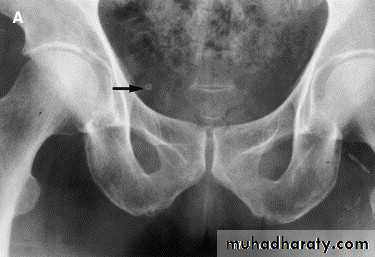

• Ddgx of stone on KUB :

• 1. Gall stone

• 2. calfied LN , cartilage ,fibroid,

• 3. Phlebolith: round, lucent centre.